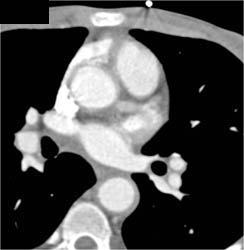

Takayasu's Arteritis